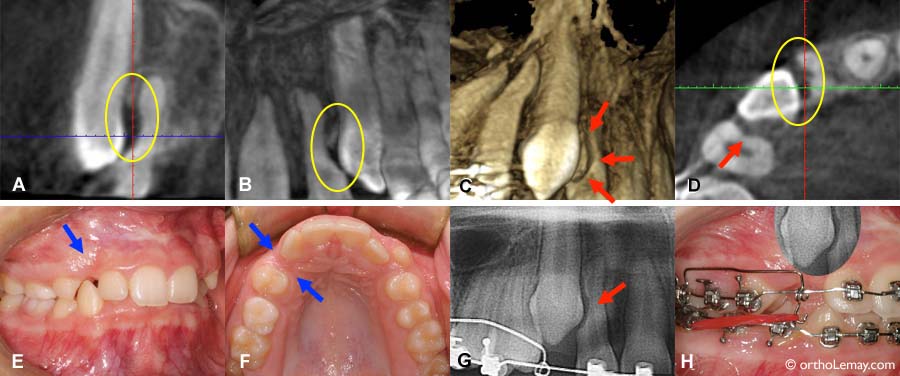

Détection de dommage aux structures avoisinantes

(A, B, C) Différentes images générées à partir d’un scan 3D montrent le dommage que cause une canine incluse sur la racine de la latérale adjacente. (D) Une vue en coupe des racines montre l’étendue de la résorption dans la racine de la latérale (cercle jaune) et une zone concave dans la racine de la prémolaire (flèche). (E, F) Endroit où se situe la canine incluse. (G) L’usure sur la racine de latérale est visible de cet angle mais pas sur la racine de la prémolaire. (H) Une superposition de la photo et de la radiographie permet d’apprécier ce qui se passe sous la gencive.